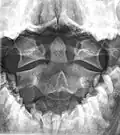

Axis on X-ray taken through an open mouth, teeth visible -